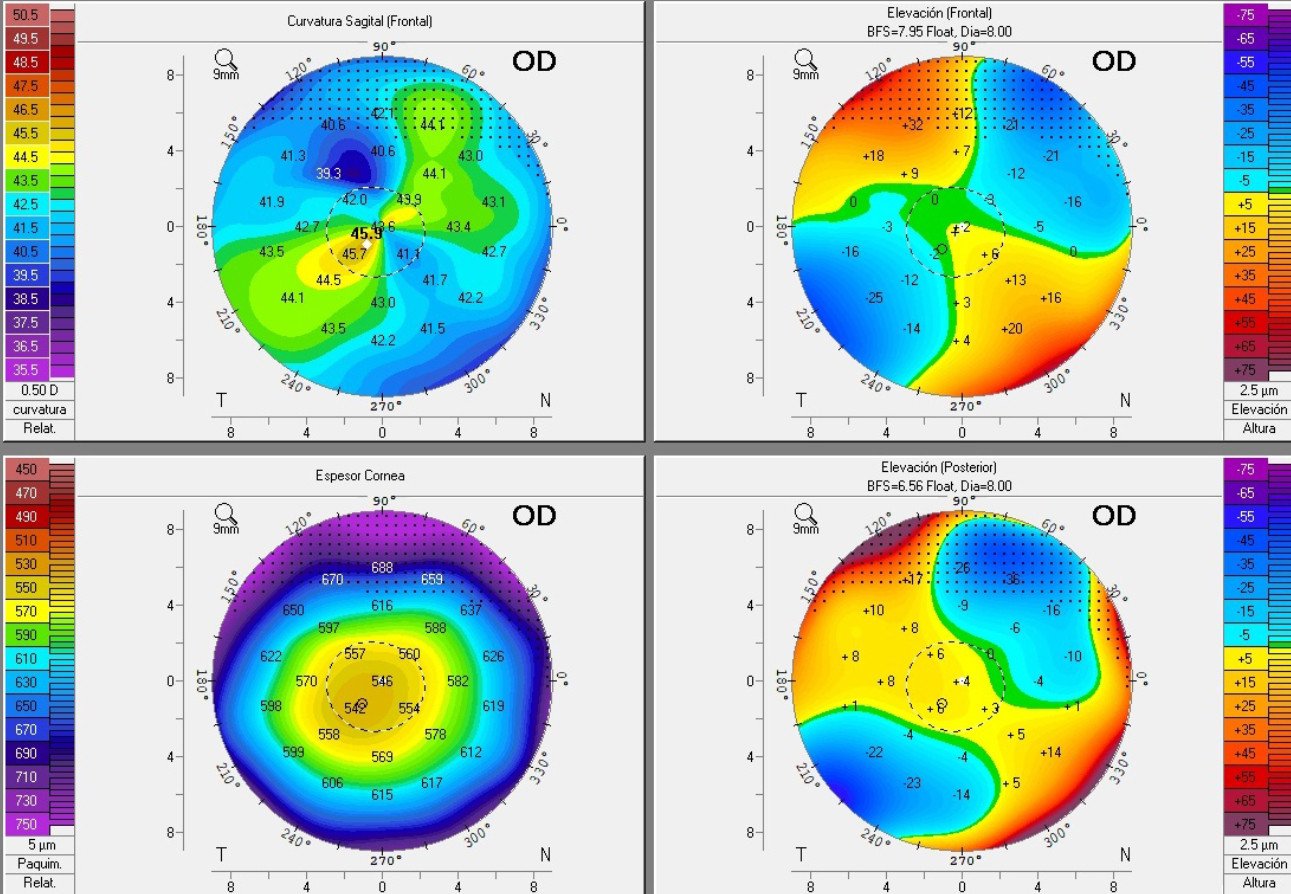

Topografía Corneal